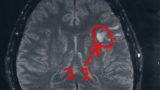

- 造影剤を注射してMRI検査

- 年レベルでおおきくなっている

- 手術して取りに行く